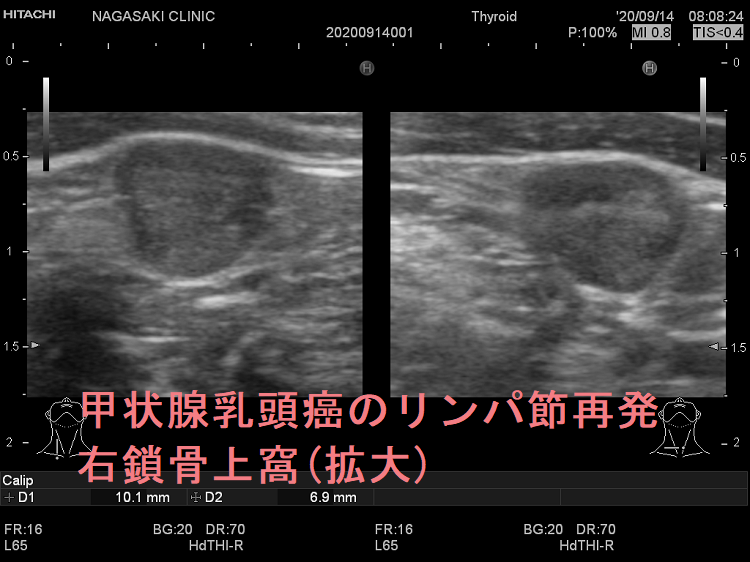

甲状腺乳頭癌のリンパ節再発 右鎖骨上窩 超音波(エコー)画像

甲状腺乳頭癌のリンパ節再発 右鎖骨上窩 超音波(エコー)画像;いびつな形で、周囲との境界が一部不明瞭化して浸潤を疑われる。リンパ門は消失し、砂粒状石灰化を認める。

甲状腺乳頭癌のリンパ節再発 右鎖骨上窩 超音波(エコー)画像(拡大)

甲状腺乳頭癌のリンパ節再発 右鎖骨上窩 超音波(エコー)画像(拡大);いびつな形で、周囲との境界が一部不明瞭化して浸潤を疑われる。リンパ門は消失し、砂粒状石灰化を認める。